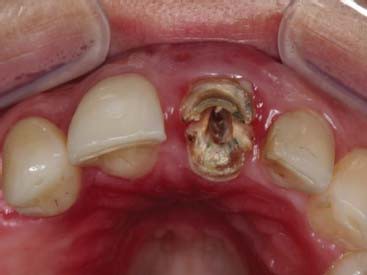

A paciente ERL, gênero feminino, 28 anos, procurou atendimento relatando dor na região anterior superior, com histórico de trauma prévio durante a mastigação. Na avaliação da paciente, o dente 21, aonde havia uma coroa cerâmica instalada com núcleo metálico, apresentava uma fratura obliqua, gengiva edemaciada, com sinais clínicos de infecção na parede vestibular do alvéolo (figura 1 e figura 2). O plano de tratamento incluiu a indicação de exodontia do dente 21, seguida de um implante imediato (Straumann® Bone Level SLActive) associado a um cicatrizador personalizado para manter a caracterização do contorno gengival do elemento.